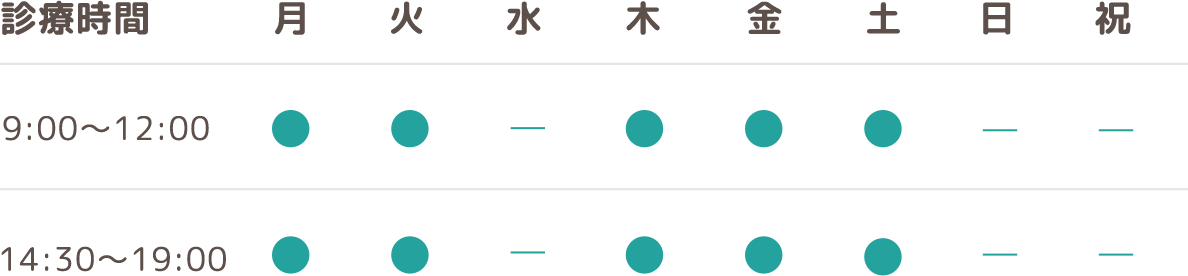

今回は 反対咬合の骨格によるタイプの分類 についてお話したいと思います。

早期反対咬合の治療では

反対咬合の改善に数カ月で完了するものと

1年数カ月掛かるタイプがあります。

この治療期間の差は何にあると思いますか?

それは骨格タイプにあるのです。

このタイプを知る為にはまず顔を横から写すレントゲンを撮ります。

そして上顎と下顎のそれぞれ底の部分がら作られる角度を診る事によって

分類する事ができます。

この角度が平行に近い程、早く治り

逆の場合は滅多な事では治す事ができません。

3歳児の顎 成人の顎